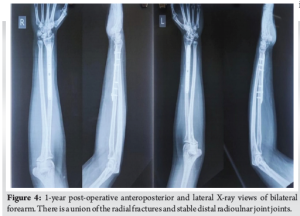

Initial management included bilateral above-elbow splints and intravenous analgesia. Following a detailed discussion with the patient, surgical intervention was planned. Open reduction and internal fixation (ORIF) was performed bilaterally under general anesthesia using a standard Henry’s approach. Both fractures were stabilized using 7-hole limited contact dynamic compression plates (LCDCPs). During surgery, anatomical fracture reduction led to spontaneous DRUJ realignment, confirmed intraoperatively through the piano key test. Fluoroscopy verified proper alignment (Fig. 2). Postoperatively, the patient was immobilized in supination with above-elbow back slabs. Three weeks later, controlled range-of-motion exercises for the wrist, elbow, and shoulder were initiated. Follow-up radiographs showed satisfactory healing. At 1 year, the patient achieved full bony union and functional recovery, scoring 95 on the Mayo wrist score.

This fracture pattern did not fit either category, highlighting the importance of meticulous radiographic evaluation for detecting unusual presentations. In pediatric patients, closed reduction and casting are often sufficient for managing Galeazzi fractures, yielding favorable results. However, in adults, surgical intervention is essential due to the strong deforming forces acting on the radius and DRUJ instability [6]. ORIF using a volar (Henry’s) approach remains the standard technique for treating Galeazzi fractures, allowing direct visualization and precise fracture stabilization [9]. In this case, 7-hole LCDCPs provided stable fixation, enabling controlled early mobilization (Fig. 2). DRUJ integrity was confirmed intraoperatively, with fluoroscopic imaging verifying proper realignment [8]. Post-operative care included immobilization in a long-arm cast for 3 weeks to prevent redislocation, followed by progressive range-of-motion exercises to minimize stiffness and optimize function. Potential complications include non-union, malunion, chronic DRUJ instability, and neuropathy. If inadequately treated, DRUJ injuries can lead to chronic pain and functional impairment, sometimes requiring salvage procedures such as the Sauvé-Kapandji or Darrach operations [10]. This patient achieved an excellent functional outcome without complications. Intraoperative assessment, including the piano key test, confirmed DRUJ stability, negating the need for additional fixation. At the 1-year follow-up, the patient exhibited full range of motion and grip strength (Fig. 3-5).